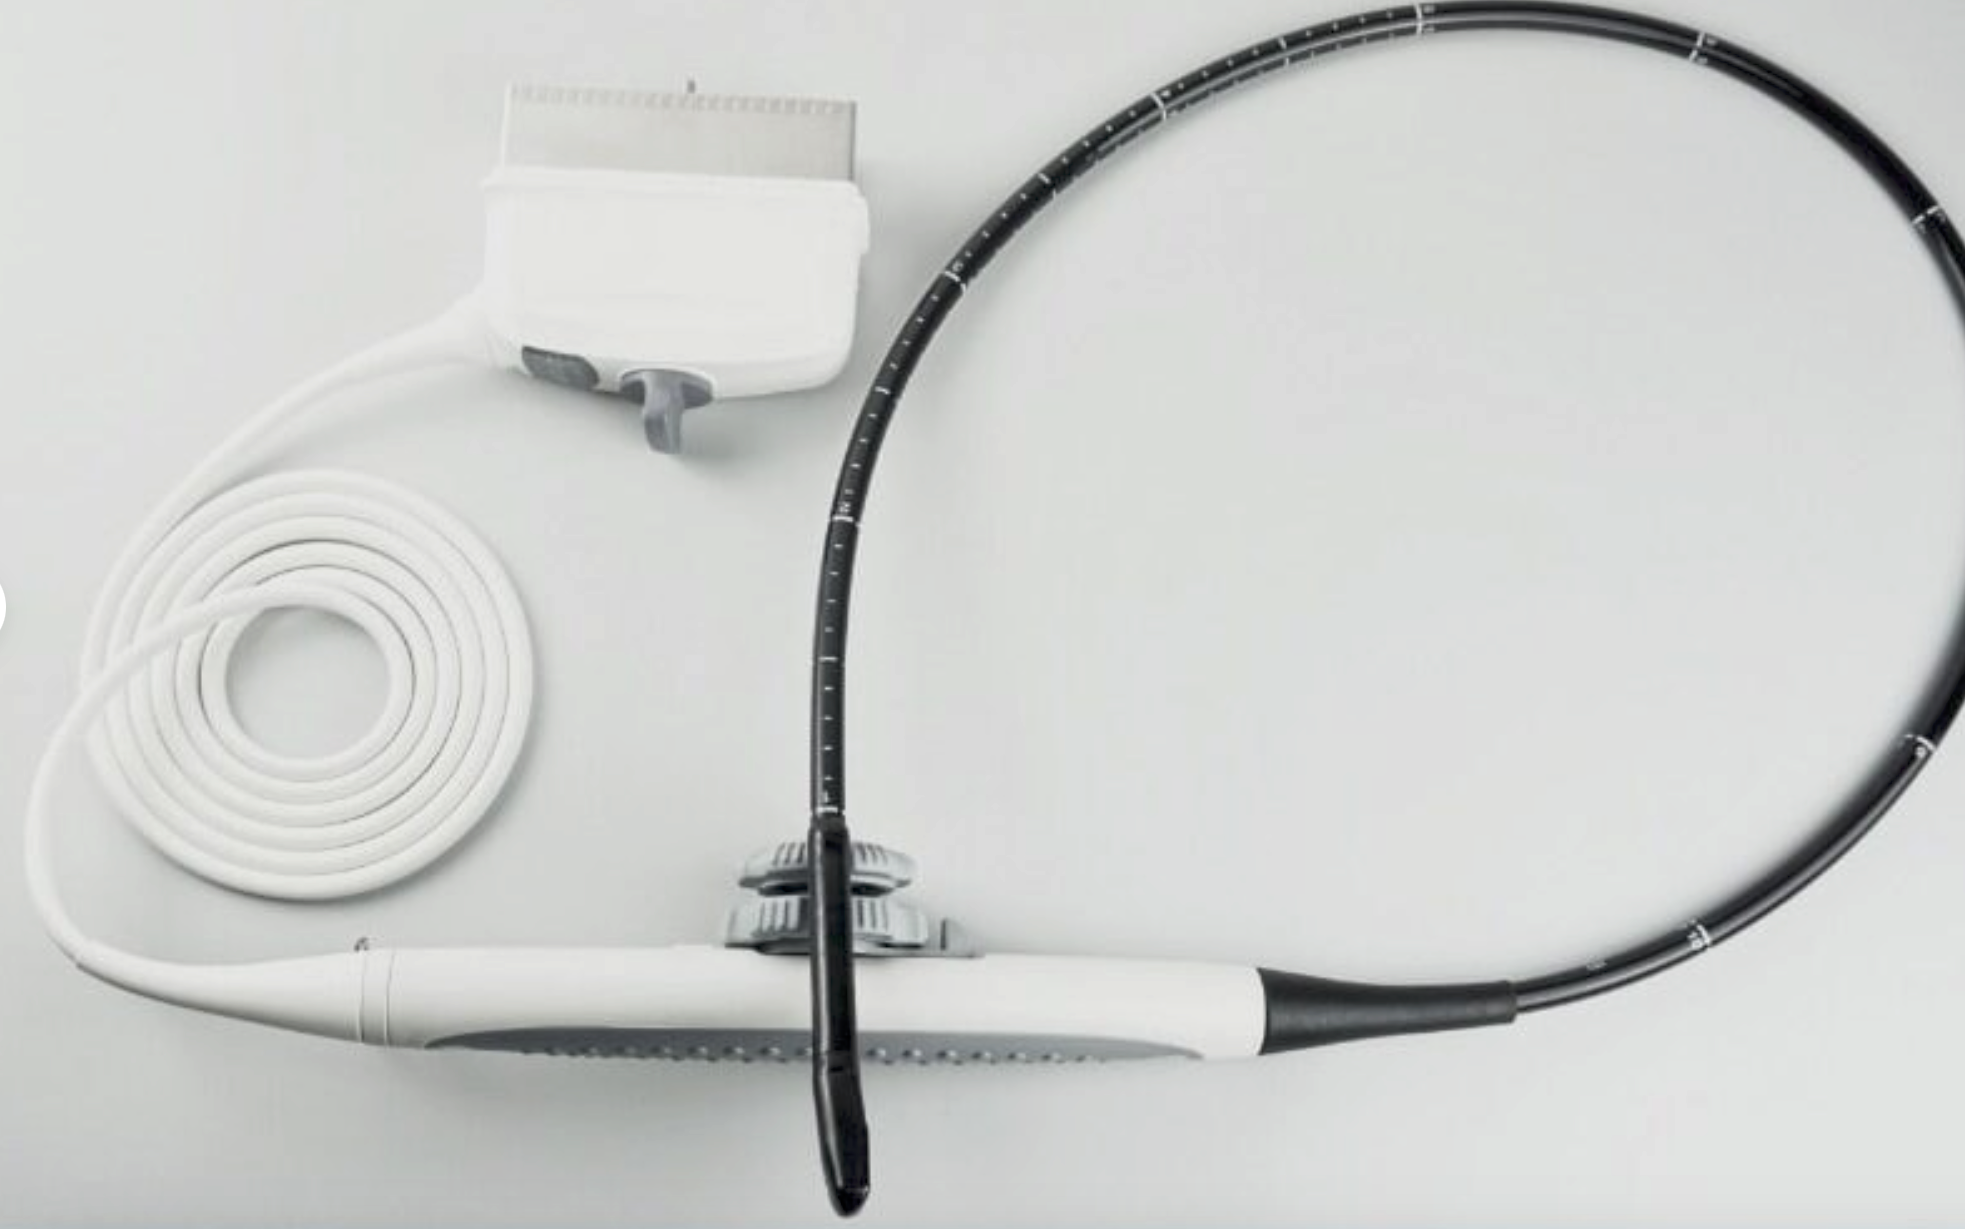

This state-of-the-art machine comes with two probes, ensuring versatility for different diagnostic needs. The SIUI Apogee 2300 supports DICOM (Digital Imaging and Communications in Medicine) which allows seamless integration with hospital information systems and ensures efficient workflow and storage management. The portability of this machine does not compromise its performance, as it delivers crystal-clear images that are critical for precise diagnostics.

In addition to its technical features, the Portable OB/GYN Ultrasound Machine is also designed with patient comfort in mind. The smooth operation and efficient scanning reduce the need for lengthy or repeated procedures, minimizing discomfort and improving patient experience. The two included probes offer flexibility in imaging, allowing for both abdominal and transvaginal examinations with ease.